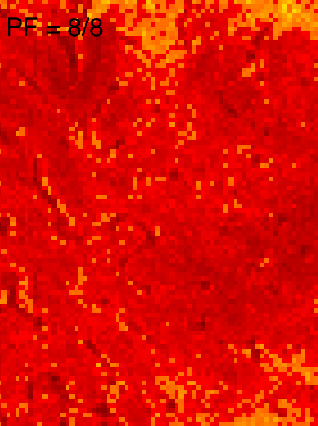

In addition to these theoretical simulations, I tried to investigate the T2*-blurring in-vivo. Two different readout strategies were used to estimate the different T2*-blurring: full k-space acquisition (readout window = 110 ms) and half k-space acquisition (readout window = 60 ms) with the same TE. In order to correct for phase inhomogeneities in the half k-space acquisition, 8% of the k-space lines were acquired symmetrically, across the center of k-space.

The experimental data confirm that full k-space acquisition appears to give better spatial specificity in the phase encoding direction than PF half k-space acquisition (Figs. M/N). Intracortical anatomical layers are blurred in the phase-encoding direction (white arrows), but not in the read direction (black arrows) for the PF half k-space GE-EPI (Fig. M). The discriminability of the intra-cortical layer-dependent signal peaks (Figs. O and P) confirms this (green arrows). Correspondingly, during a finger tapping task, the functional profiles delineated layer-dependent responses with higher effective resolution for the full k-space GE-EPI scheme compared to the case where T2*-attenuation is symmetric in k-space (Figs. Q/R).